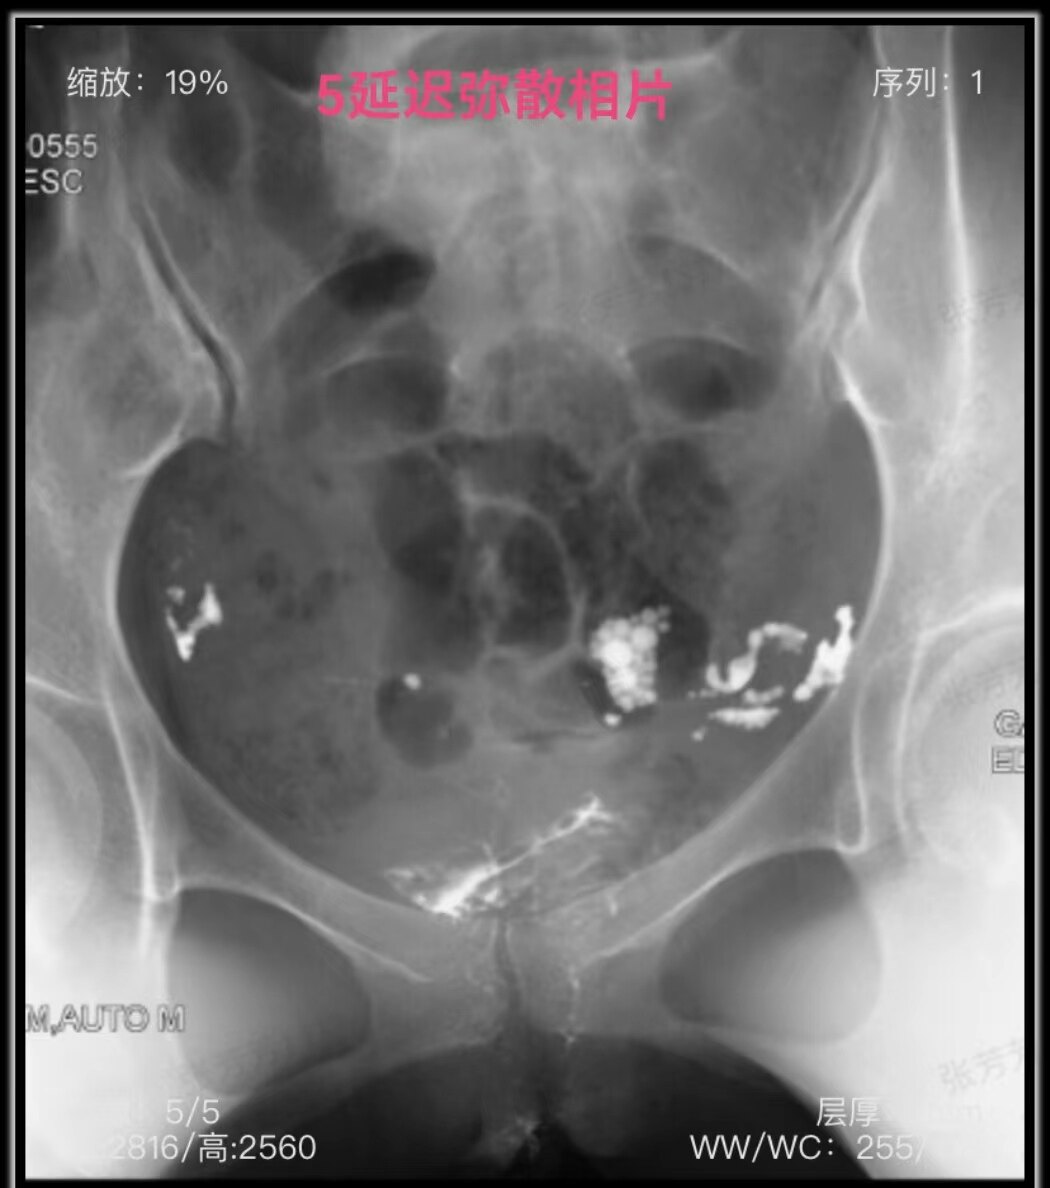

1.jpg

盆腔平片